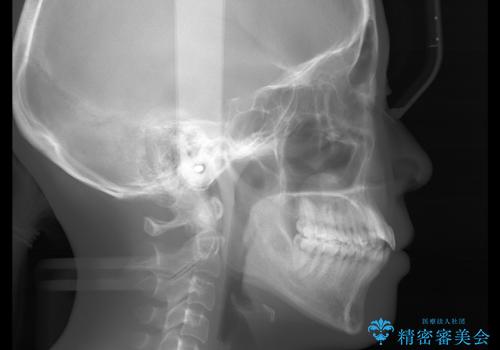

- 以前からコンプレックスだった八重歯の治療を主訴にご来院されました。

検査の結果、抜歯をすることでスペースを作って並べる方法が選択され、ワイヤー装置を用いた治療を開始することとなりました。

奥歯の上下のズレ等は軽度で、必要なスペースと抜歯により作られるスペースがほぼ等量だったため治療の単純化が計れ、大きな移動・見た目の劇的な変化に対して比較的早期での治療完了となりました。

叢生の度合いが重く、抜歯が必要なケース。八重歯の部分以外には大きな問題は認められなかったため、劇的変化が起こる治療でも比較的短期間で終了することができました。